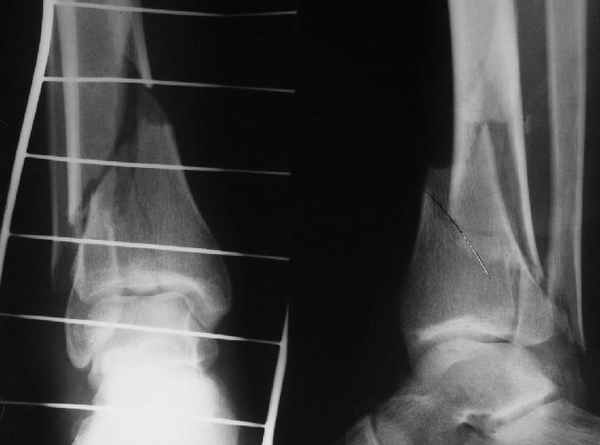

Да и нет! Зависит от перелома и способа остеосинтеза. А результат? (01)

А.Миронов

Кликните для загрузки файла 01.jpg

65KB (66785 bytes)

Мы же говорили о проксимальном плече. При переломе tibia, конечно, речи о двух Y-спицах нет. Еще раз о них - пружинящая подвижность без "срезающих" перемещений фрагментов - дополнительный стимул к образованию периостальной мозоли.

А в данном случае - у нас был бы применен locked nail с еще меньшими дырочками на коже и с возможностью полной нагрузки немедленно после операции. Какие тут аргументы в пользу выбора пластины, а не интрамедуллярного гвоздя?